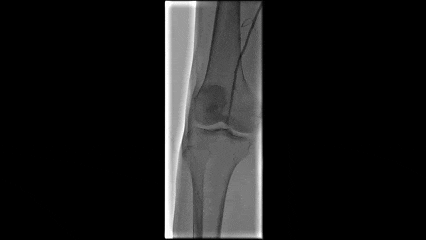

最终结果

最终造影证实血流通畅,管腔获得满意,远端无栓塞证据。

药物球囊应用

切除后造影显示管腔获得良好,使用6-4药物球囊进行后扩张。